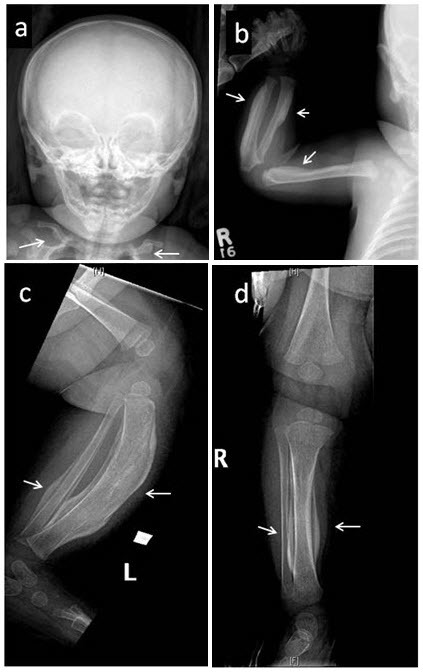

Figure 1. . Skeletal survey in a female age five weeks with the defining COL1A1 p.

圖1:對一名五周齡女性進行的骨骼調(diào)查,該女性具有明確的 COL1A1 p.Arg1014Cys 致病性變異,其右脛骨出現(xiàn)疼痛性腫脹。注意廣泛參與 (a) 涉及下頜骨和鎖骨的對稱雙側(cè)骨膜反應; (b) 肱骨、橈骨近端軸和尺骨遠端軸的不對稱受累; 和 (c,d) 脛骨和腓骨。箭頭指向顯著的骨膜下增厚和彎曲。 還注意到髂骨、股骨、脛骨和左腓骨的不對稱反應(未顯示)。 癥狀在發(fā)作后一個月內(nèi)消失。